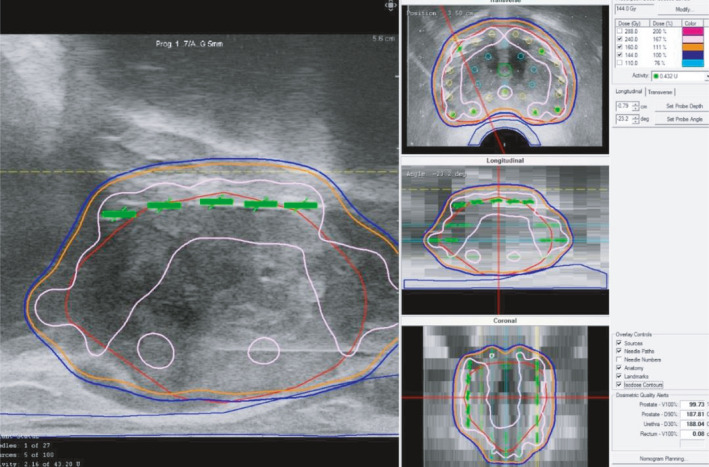

【 Step ⑩ 】As the final step, we check the entire dose distribution for all 2D views (sagittal, transverse, coronal) and confirm that the entire prostate target is covered with 160 Gy [Fig. 10(a)].

Fig. 10.

Final step: confirmation of dosimetry. (a): As the final step, check the entire dose distribution for all 2D views and confirm that the entire prostate target is covered with 160 Gy (orange). Note that the high‐dose band (240 Gy, pink) does not invade the urethra and rectum C (b): Confirm parameters including OAR.

Note that the high‐dose cloud (240 Gy) does not invade the urethra and rectum.

D90 should be over 190 Gy and V100 should be over 99%. Upon OAR parameters, UD30 should be under 215 Gy and R100 should be under 0.5cm3 [Fig. 10(b)].